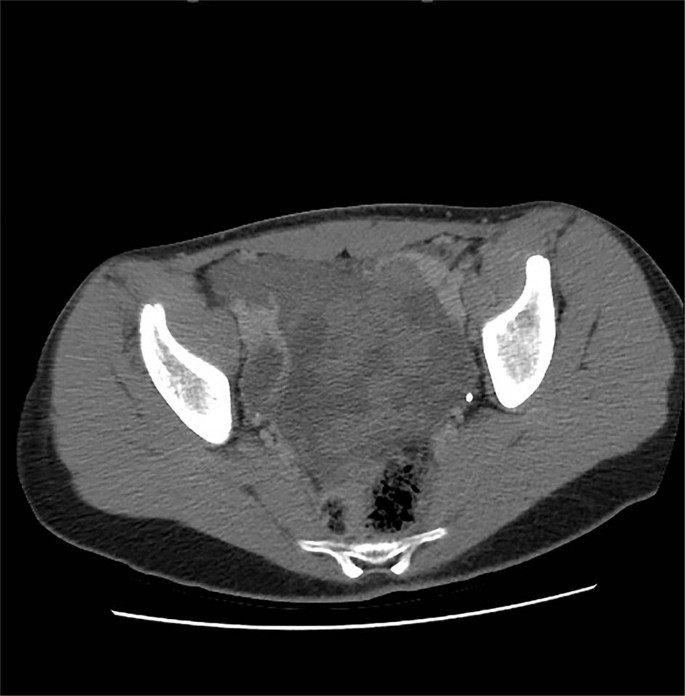

Case 1: a 13-year-old girl with no significant medical history presented with severe, generalized abdominal pain. Computed tomography (CT) scan demonstrated a multi-loculated cystic mass in the pelvic cavity (Fig. 1). Intraoperatively, a hemorrhagic mass involving the left fallopian tube was excised en bloc. Histologically, the tumor resembled a type I PPB (Fig. 2a). She was treated with four cycles of vincristine, actinomycin D, and cyclophosphamide (VAC) followed by the four cycles of vincristine and actinomycin D and second look surgery; she remains disease free 30 months following original resection. In addition, she was found to have Bethesda category II thyroid nodules; fine needle aspiration/biopsy was negative for malignant cells.

Axial computed tomography images demonstrate a heterogeneous low attenuation intraperitoneal lesion within the pelvis with peripheral areas of decreased attenuation and areas with higher attenuation consistent with solid components, embedded bowel or a combination.